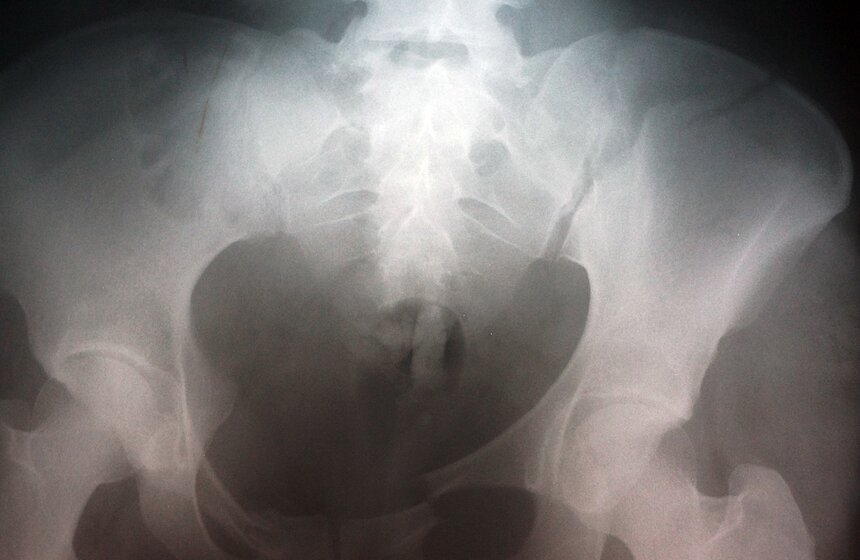

Фото: m24.ru